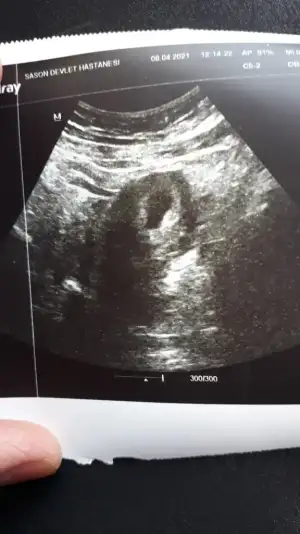

Meraba kızlar bugün ilk ultrason Muaynemi oldum kese göründü ama bebek görünmüyor dedi doktor çok kötü oldum acama boş gebelik mi erken mi tüp bebek le oldu benim bugün 5+5 günlük

Karından ultrason la baktı alttan bakalım falan demeyince bende söylemedim cihazımız eski yada daha küçük oldupu için görünmüyordur normal dedi ama ben daha önce boş gebelik geçirdiğim için ödüm kopuyor yine aynıysa diye.